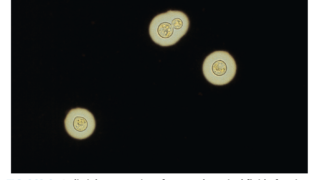

m.3243A>G変異はスクリーニングはEDTA血液サンプルを使って行われることが多いが、血液中のヘテロプラスミーのレベルが検出下限以下であることがある。その場合は尿路上皮細胞や骨格筋など他の組織での検査が必要となる場合がある。